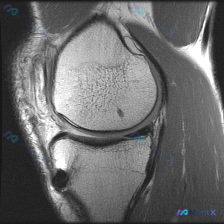

这是一张膝关节T1加权矢状位MRI图像,对比度良好,显示膝关节前部结构:髌骨、股骨远端滑车、胫骨近端和髌下脂肪垫,左侧为前侧,右侧为后侧,上为头侧下为足侧。

- 骨骼与骨髓:髌骨、股骨远端、胫骨近端皮质轮廓完整,无骨折,骨髓信号正常,是典型黄骨髓脂肪信号,没有局灶性异常低信号区(除了后面提到的两处病灶)

- 关节软骨:髌股关节面和胫骨平台软骨轮廓平滑,没有明显的局部软骨缺损或剥脱

- 韧带肌腱:髌腱走行连续,信号正常,没有增粗、肿胀或中断

- 髌下脂肪垫:形态和信号都没有异常

- 关节腔与软组织:没有明显关节积液,周围软组织也没有肿胀水肿

这张图像上一共发现两处异常:

- 股骨远端滑车面软骨下骨质内,有一个边界清晰的局灶性点状T1低信号影

- 胫骨结节前方的软组织/骨皮质边缘,同样有一个局灶性低信号影

其余结构没有看到明确异常,半月板因为层面问题只能看到部分轮廓,没有发现明显信号异常。